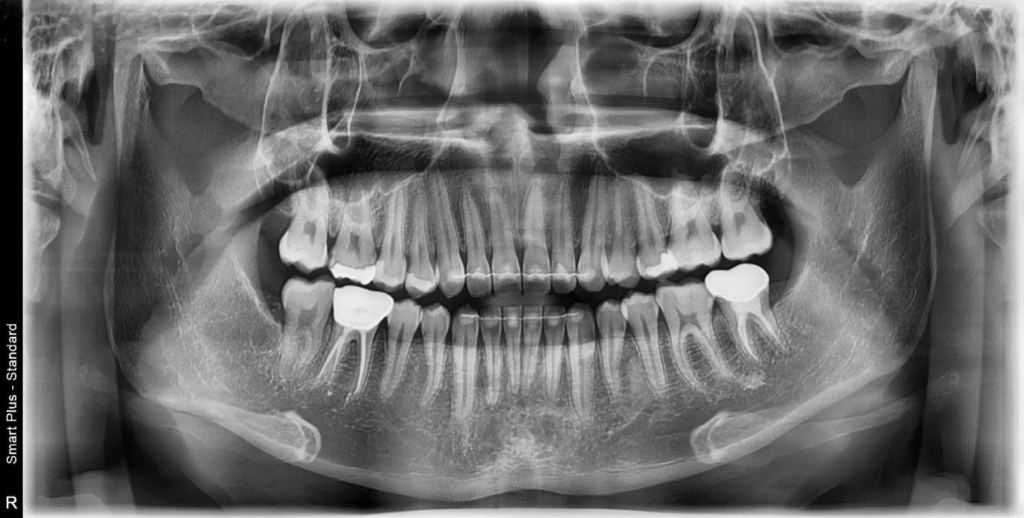

이번에도 마찬가지로 3개월 가량이 되어 스케일링 및 검진을 위해 최근 개원한 치과에 초진을 보러 갔고 엑스레이 사진 상 왼쪽 위 앞쪽 뒷쪽 어금니에 인레이 치료 두 개 오른쪽 아래에 치아 마모된 부분은 레진 치료 진행해야 한다고 하시더군요

치아 번호로 말씀드리면 24번 27번 인레이 치료(필수) + 25,26번 레진(인레이 치료 도중 충치 발견시 레진 치료 가능성 높음) + 45번 치아 마모된 부분 레진 치료 이렇게 진단을 받았습니다.

엑스레이 상으로만은 정확히 판단은 어렵지만, 26, 27번사이에 약간 충치가 잇어 보이긴합니다. 24번은 치아가 겹쳐 보여서 엑스레이 상으로는 확ㅇㄴ이 어렵네요. 그리고 45번의 경우는 시리다면 치경부 치료를 하시는게 좋습니다.